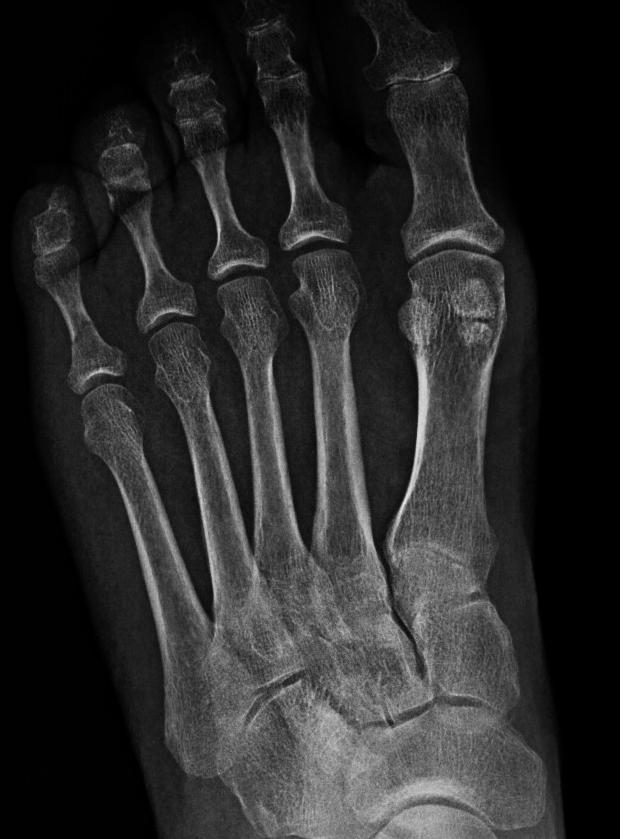

Las articulaciones metatarsofalángicas están situadas entre las lisas y redondeadas cabezas de los huesos metatarsianos y la cavidad poco profunda de la base de la falange proximal. Son articulaciones condileas sinoviales, rodeadas por una cápsula articular bastante holgada, revestida por una membrana sinovial.

The metatarsophalangeal joints are ellipsoid synovial joints between the sphere-shaped head of the metatarsal and the corresponding bases of the proximal phalanges of the digits. The metatarsophalangeal joints allow extension and flexion, and limited abduction, adduction, rotation, and circumduction.